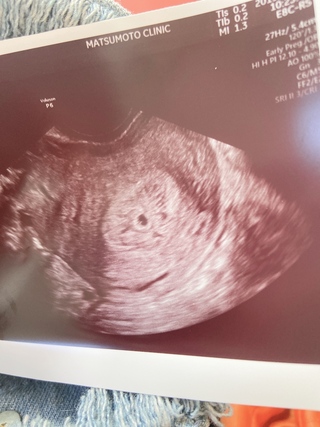

妊娠5週目 5w0d 6d のエコー写真とエピソード 妊娠2ヶ月 Cozre コズレ 子育てマガジン

画像見て判断してください 5週4日 エコー写真です正常妊娠としか言 Yahoo 知恵袋

妊娠5週 エコーで胎嚢が確認できる 妊娠初期症状や過ごし方 ままのて